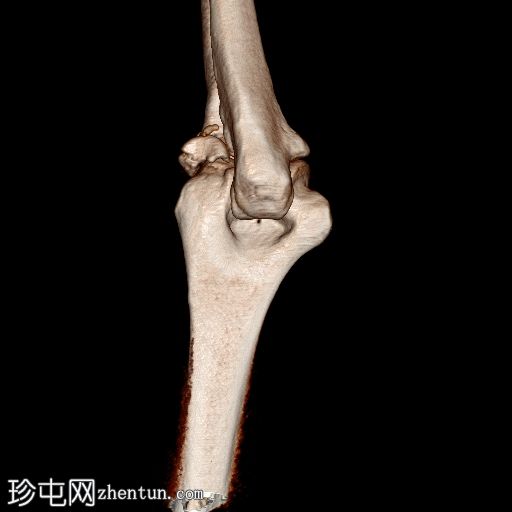

3D平扫

显示整个桡骨头粉碎性骨折,特征为两个以上大骨折块,以及倾斜且受压的关节节。

这表明该骨折为不稳定骨折,根据Mason桡骨头骨折分型,为IIIC型。

远端肱骨和可见尺骨未见骨折征象。

此外,由于关节积血导致关节扩张,肘关节脂肪平面弯曲。

对于 Mason IIIc 型骨折,如本例,需要切开复位内固定 (ORIF)。